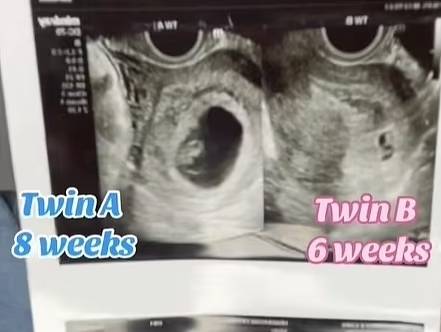

지난 19일 데일리메일 등 외신에 따르면, 텍사스에 거주하는 테일러 헨더슨(28)은 지난해 임신 8주차에 초음파 검사를 통해 쌍둥이가 아닌 두 명의 아이를 임신한 사실을 확인했다.

헨더슨은 “산부인과에서 초음파 검사를 받았는데, 크기가 다른 태아가 있는 것을 발견했다”며 “이들은 쌍둥이가 아니었다”고 말했다. 그는 이어 “한 태아는 8주 전에 임신이 됐고, 또 다른 태아는 그 후인 6주 전에 임신이 된 거였다”며 “임신 후 성관계를 가졌었는데 그때 임신이 된 것 같다”고 밝혔다.

이에 대해 의료진은 헨더슨에게 ‘중복 임신’(superfetation)이라고 진단하면서, 중복 임신 사례를 실제로 본 적은 없다며 놀라워했다.